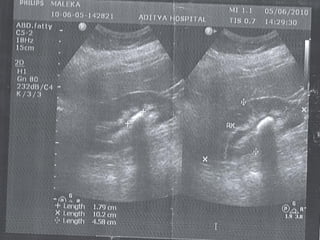

โ€ข ULTRASONOGRAPHY

โ€ข HYDRONEPHROSIS

โ€ข HYDROURETER โ€“ UPPER / LOWER

โ€ข CALCULI โ€“ RENAL / PUJ / URETER

โ€ข PARENCHYMAL THICKNESS

โ€ข URETERIC JET

โ€ข RENAL RESISTIVE INDEX